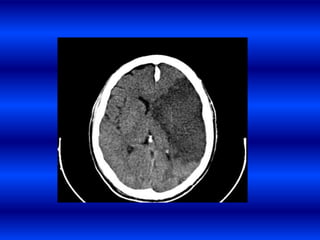

Encefalopatía hipertensiva

• Síndrome de disfunción difusa asociada a una

elevación repentina o severa de la presión

arterial sistémica.

Causa

• Falla en la autorregulación cerebral con

hiperperfusión y subsecuente edema encefálico,

hemorragias petequiales y necrosis arteriolar.